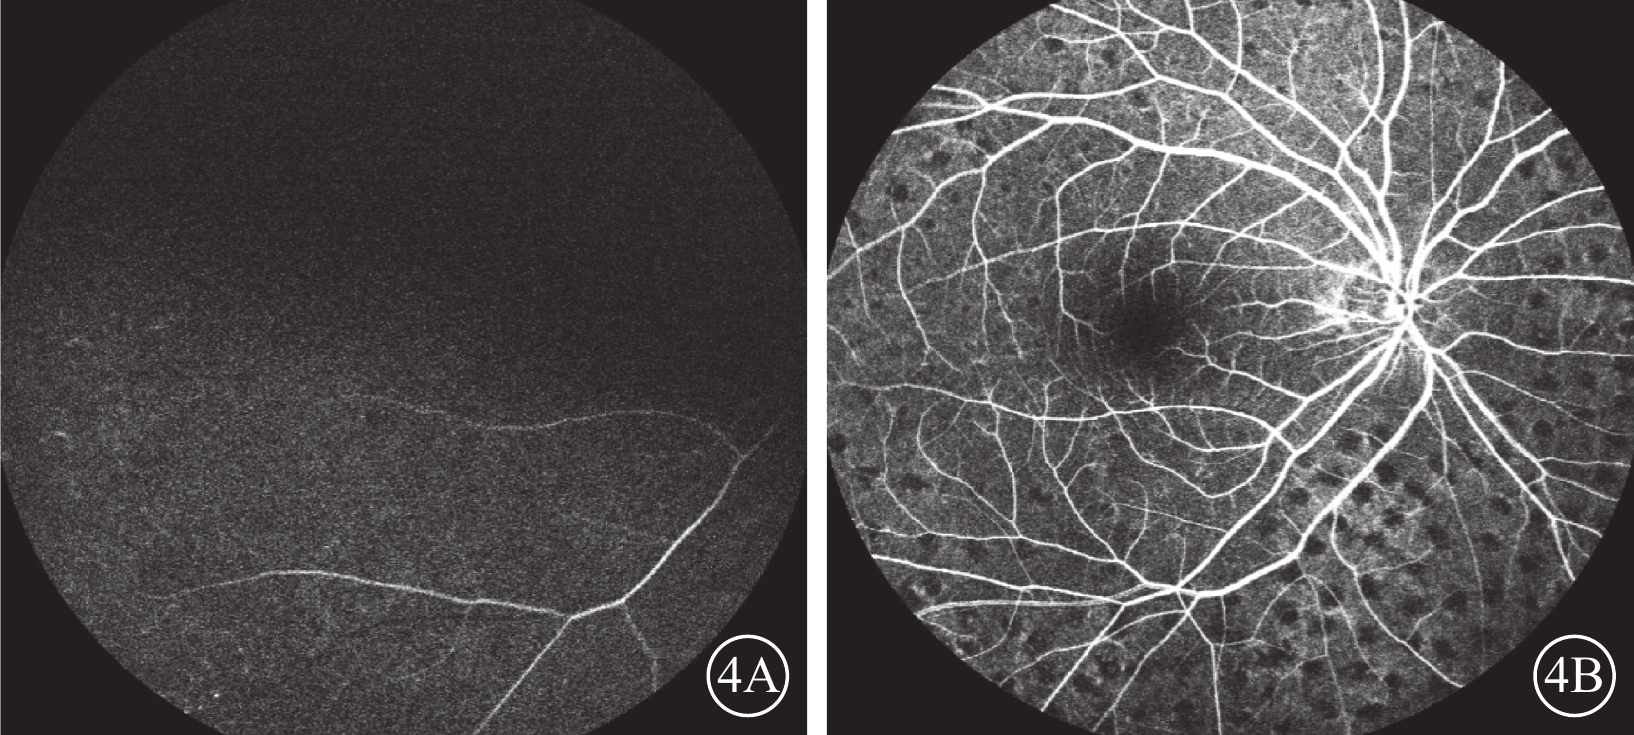

圖4

右眼治療后FFA像。4A. 12.75 s,視網膜中央動脈完全充盈;4B. 18.57 s,視網膜中央靜脈完全充盈

圖4

右眼治療后FFA像。4A. 12.75 s,視網膜中央動脈完全充盈;4B. 18.57 s,視網膜中央靜脈完全充盈

圖4

右眼治療后FFA像。4A. 12.75 s,視網膜中央動脈完全充盈;4B. 18.57 s,視網膜中央靜脈完全充盈

圖4

右眼治療后FFA像。4A. 12.75 s,視網膜中央動脈完全充盈;4B. 18.57 s,視網膜中央靜脈完全充盈

患者男,65歲。因右眼視物不見1周于2016年10月20日來我院就診。1周前無意中發現右眼視物不見,無眼紅、痛、畏光、流淚;自行使用芐達賴氨酸(商品名:莎普愛思)滴眼液滴眼無效而就診于外院。診斷為右眼新生血管性青光眼(NVG)?右眼視網膜病變(性質?);雙眼老年性白內障。既往高血壓病史8年,口服藥物治療。否認糖尿病、冠心病等其他全身病史。眼科檢查:右眼視力光感/眼前;左眼視力0.6,不能矯正。右眼眼壓17.3 mmHg(1 mmHg= 0.133 kPa),左眼眼壓12.7 mmHg。右眼前房深淺正常,周邊前房1 角膜厚度;瞳孔藥物性散大,邊緣全周可見虹膜新生血管(NVI),無后粘連;晶狀體混濁;玻璃體輕度混濁。眼底視盤邊界清楚,顏色橘紅,血管走形及比例基本正常;視網膜可見散在點片狀出血及片狀棉絨斑,黃斑中心凹反光不清(圖1)。左眼除晶狀體混濁、玻璃體輕度混濁,黃斑中心凹反光不清外,其余眼前節及眼底檢查未見明顯異常。熒光素眼底血管造影(FFA)檢查,右眼脈絡膜背景熒光充盈遲緩,視網膜動靜脈循環時間明顯延長(圖2)。光相干斷層掃描檢查,右眼后極部視網膜增厚,視網膜內層間反射信號大部分增強;左眼黃斑中心凹形態不規則。彩色超聲多普勒血流成像(CDFI)檢查,雙側頸總動脈、頸內動脈多發斑塊;右側頸內動脈管腔狹窄,約70%~99%(圖3)。頸動脈CT血管造影(CTA)檢查,顱內動脈硬化,可疑右側頸內動脈C1段重度狹窄;可疑兩側基底節區、右側丘腦腔隙性缺血灶。診斷:右眼眼缺血綜合征(OIS);雙眼老年性白內障;高血壓病。給予右眼玻璃體腔注射雷珠單抗0.05 ml治療。治療后3 d,視力數指/66 cm,眼壓15.0 mmHg;NVI完全消退。行右眼全視網膜激光光凝(PRP)治療。PRP治療后14 d檢查,右眼視力0.1;眼壓13.0 mmHg。轉血管外科行右側頸動脈內膜剝脫手術。手術后1個月復查,右眼視力0.4。FFA檢查,視網膜循環時間明顯改善(圖4)。

患者男,65歲。因右眼視物不見1周于2016年10月20日來我院就診。1周前無意中發現右眼視物不見,無眼紅、痛、畏光、流淚;自行使用芐達賴氨酸(商品名:莎普愛思)滴眼液滴眼無效而就診于外院。診斷為右眼新生血管性青光眼(NVG)?右眼視網膜病變(性質?);雙眼老年性白內障。既往高血壓病史8年,口服藥物治療。否認糖尿病、冠心病等其他全身病史。眼科檢查:右眼視力光感/眼前;左眼視力0.6,不能矯正。右眼眼壓17.3 mmHg(1 mmHg= 0.133 kPa),左眼眼壓12.7 mmHg。右眼前房深淺正常,周邊前房1 角膜厚度;瞳孔藥物性散大,邊緣全周可見虹膜新生血管(NVI),無后粘連;晶狀體混濁;玻璃體輕度混濁。眼底視盤邊界清楚,顏色橘紅,血管走形及比例基本正常;視網膜可見散在點片狀出血及片狀棉絨斑,黃斑中心凹反光不清(圖1)。左眼除晶狀體混濁、玻璃體輕度混濁,黃斑中心凹反光不清外,其余眼前節及眼底檢查未見明顯異常。熒光素眼底血管造影(FFA)檢查,右眼脈絡膜背景熒光充盈遲緩,視網膜動靜脈循環時間明顯延長(圖2)。光相干斷層掃描檢查,右眼后極部視網膜增厚,視網膜內層間反射信號大部分增強;左眼黃斑中心凹形態不規則。彩色超聲多普勒血流成像(CDFI)檢查,雙側頸總動脈、頸內動脈多發斑塊;右側頸內動脈管腔狹窄,約70%~99%(圖3)。頸動脈CT血管造影(CTA)檢查,顱內動脈硬化,可疑右側頸內動脈C1段重度狹窄;可疑兩側基底節區、右側丘腦腔隙性缺血灶。診斷:右眼眼缺血綜合征(OIS);雙眼老年性白內障;高血壓病。給予右眼玻璃體腔注射雷珠單抗0.05 ml治療。治療后3 d,視力數指/66 cm,眼壓15.0 mmHg;NVI完全消退。行右眼全視網膜激光光凝(PRP)治療。PRP治療后14 d檢查,右眼視力0.1;眼壓13.0 mmHg。轉血管外科行右側頸動脈內膜剝脫手術。手術后1個月復查,右眼視力0.4。FFA檢查,視網膜循環時間明顯改善(圖4)。